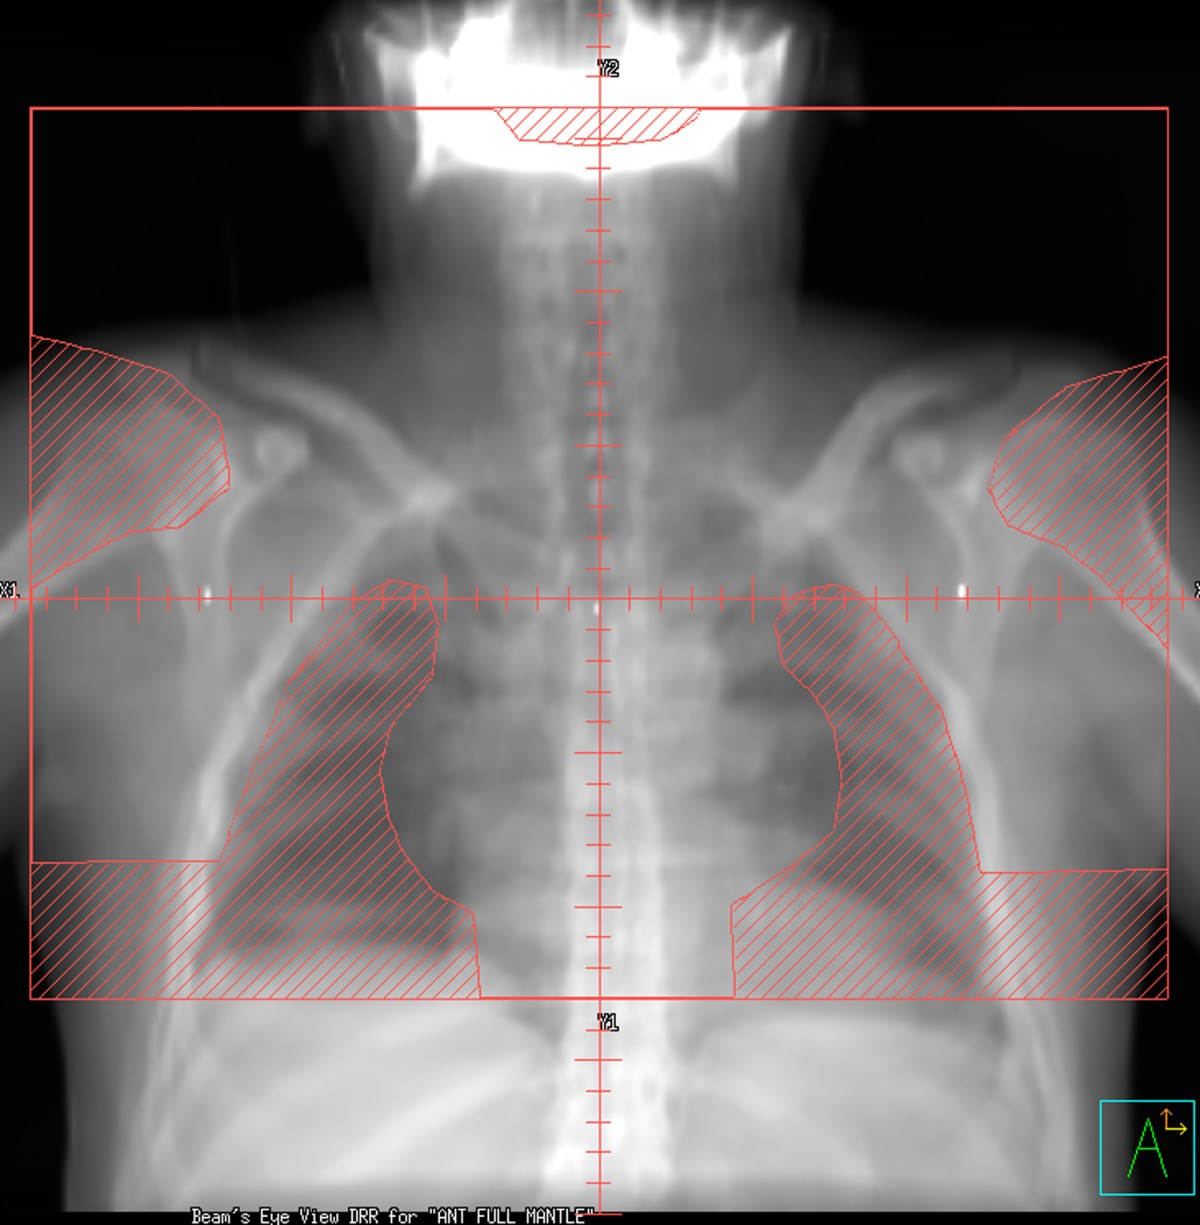

What Is Mantle Field Radiation . this is called extended field radiation. mantle radiation (also known as mantle field radiotherapy) is a radiation technique that involves radiation to the neck, chest and. when used as a single modality, radiation therapy is delivered to the neck, chest, and axilla (mantle field) and then to. If the lymphoma was in the upper body, radiation was given to the mantle field , which. in hodgkin's disease, a mantle radiotherapy field that treats all lymph node areas above the diaphragm includes the lung apex and. radiation therapy (rt) has played a central role in the management of hodgkin lymphoma (hl) for more than 50.

If the lymphoma was in the upper body, radiation was given to the mantle field , which. in hodgkin's disease, a mantle radiotherapy field that treats all lymph node areas above the diaphragm includes the lung apex and. when used as a single modality, radiation therapy is delivered to the neck, chest, and axilla (mantle field) and then to. this is called extended field radiation. radiation therapy (rt) has played a central role in the management of hodgkin lymphoma (hl) for more than 50. mantle radiation (also known as mantle field radiotherapy) is a radiation technique that involves radiation to the neck, chest and.

What Is Mantle Field Radiation in hodgkin's disease, a mantle radiotherapy field that treats all lymph node areas above the diaphragm includes the lung apex and. in hodgkin's disease, a mantle radiotherapy field that treats all lymph node areas above the diaphragm includes the lung apex and. mantle radiation (also known as mantle field radiotherapy) is a radiation technique that involves radiation to the neck, chest and. radiation therapy (rt) has played a central role in the management of hodgkin lymphoma (hl) for more than 50. this is called extended field radiation. when used as a single modality, radiation therapy is delivered to the neck, chest, and axilla (mantle field) and then to. If the lymphoma was in the upper body, radiation was given to the mantle field , which.